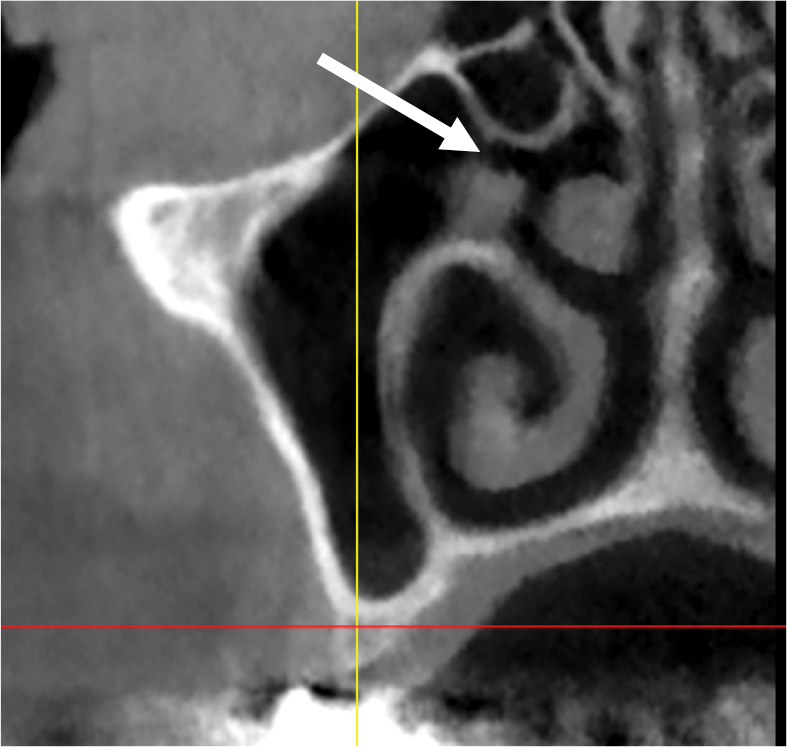

Concha, or Turbinates

In the nose, there is an inferior, middle, and superior turbinate (Figure 24). These structures are also called concha. The inferior turbinate is an independent facial bone, whereas the middle and superior turbinates are part of the ethmoid bone. When the mucosa around a turbinate is inflamed, the turbinate appears distended.

Fig 24. Turbinate bones: cross-sectional view. They are found within the nose. There is an inferior (A), middle (B), and superior turbinate (C).

Figure 24